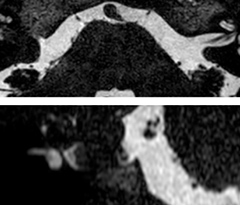

Excellent spine and spinal cord imaging

Looking for inflammatory lesions of the spinal cord is usually challenging with MRI, says Dr. Savatovsky. “We solved some of the challenges by implementing sequences such as 3D PSIR, which allows us to see far more lesions than the usual T2 imaging. We are starting to see cases where the MRI images at 1.5T were normal, but then we do see lesions when performing the PSIR at 3.0T.” [1]

“Elition also performs very well in imaging of the bony spine, the discs and degenerative disease, especially now that we can include at least one 3D sequence in every scan. For example, we perform a lot of 3D spin-echo (TSE) sequences when imaging degenerative lumbar spines. Thanks to Compressed SENSE and the 3D SpineVIEW protocols, we have a very high signal intensity with no flow voids, so the image quality is very good. The possibility to reformat the images in every plane raises the diagnostic confidence, especially in patients who have to undergo surgery.”